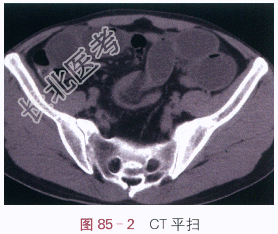

读片分析:X光平片显示小肠充气、扩张,并显示弹簧样黏膜,表现为小肠肠梗阻;CT扫描显示盆腔局部小肠靶征及肿块,近端小肠充气扩张、积液伴气液平面,远端小肠萎陷。